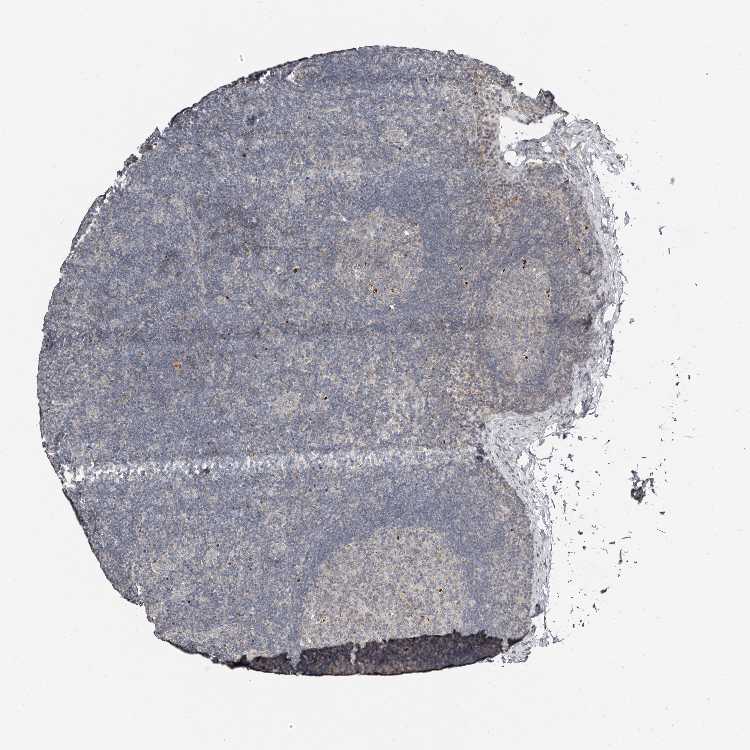

TISSUE PRIMARY DATA LYMPH NODE Show tissue menu

Lymph node

LYMPH NODE - Antibody stainingi

Antibody staining in the annotated cell types in the current human tissue is reported as not detected, low, medium, or high, based on conventional immunohistochemistry profiling in selected tissues. This score is based on the combination of the staining intensity and fraction of stained cells.

Each image is clickable and will lead to virtual microscopy that enables deeper exploration of all samples and also displays staining intensity scores, fraction scores and subcellular localization as well as patient and tissue information for each sample.

Antibody HPA029165Antibody HPA029167Antibody CAB028574

Germinal center cells Not detectedLowNot detected

Non-germinal center cells LowMediumNot detected